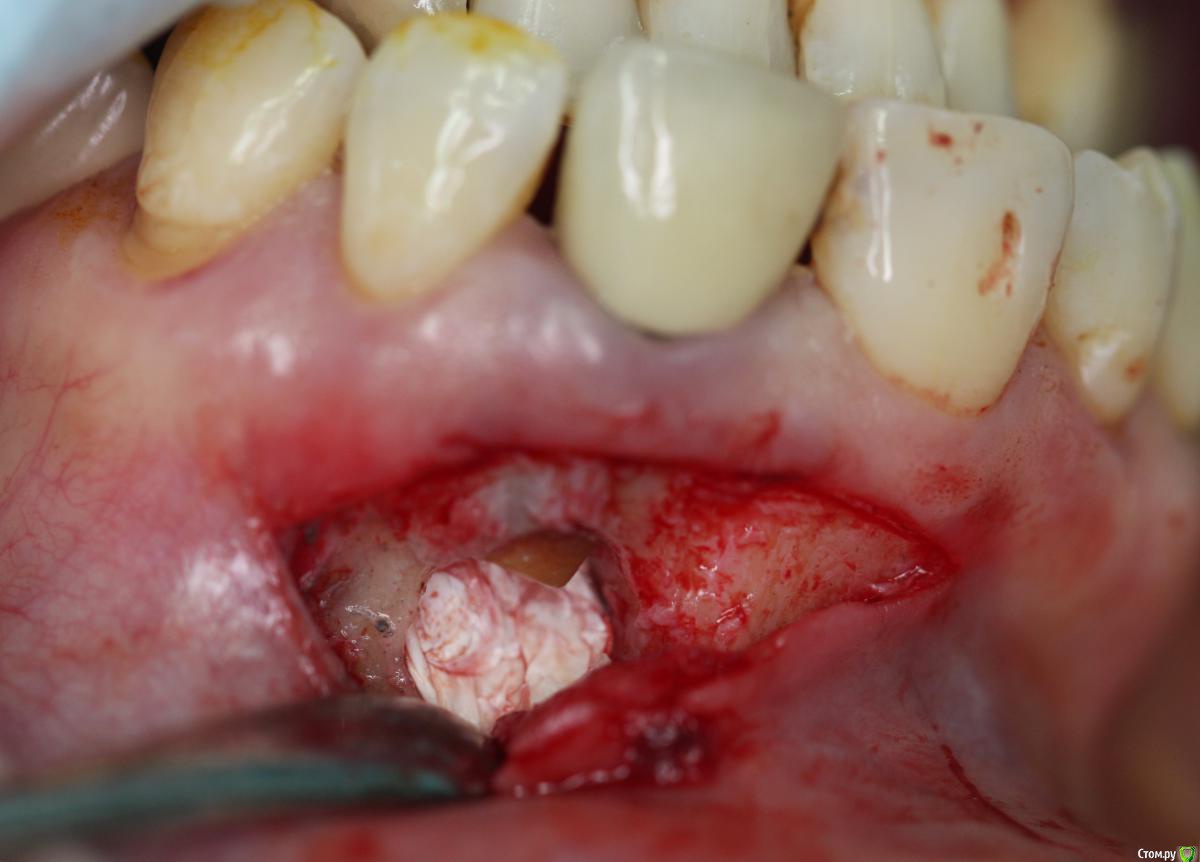

Zorrro Опубликовано 31 мая, 2016 Поделиться Опубликовано 31 мая, 2016 Во время резекций иногда хорошенько заливает,коагулятор у меня не всегда решает этот вопрос,как и ватные шарики с адреналином…Хочу с вами поделиться тем,что мне взбрело в голову,может кому-то пригодится.Взяв проавтоклавируемую фум ленту ,утрамбовал её с помощьюгладилки на дно полости.Кровотечение остановилось,позволив мне высушить зуб перед ретроградной пломбировкой. 13 Ссылка на комментарий